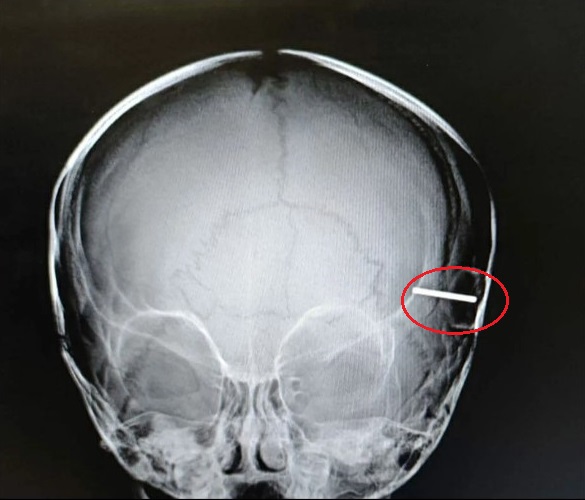

Kết quả chụp X-quang cho thấy thanh kim loại được gắn trên bánh xe đồ chơi đã đâm sâu vào hộp sọ của bé gái đến vài centimet và đã chạm vào đến não. Tức thì, các bác sĩ đã tiến hành phẫu thuật để lấy dị vật ra khỏi đầu của bé gái.

Kết quả X-quang cho thấy thanh kim loại đã đâm sâu vài centimet vào trong hộp sọ của đứa trẻ.

Bác sĩ phẫu thuật Ruslan Molotov cho biết: "Ban đầu chúng tôi rất lo sợ thanh kim loại đã làm tổn thương não của đứa trẻ. Nhưng sau khi hội chẩn, chúng tôi đã quyết định dùng một dụng cụ đặc biệt để lấy dị vật ra nhưng không làm tổn thương bề mặt não. May mắn là nó thành công. Bé gái sẽ không bị tổn thương lâu dài từ vụ tai nạn này".